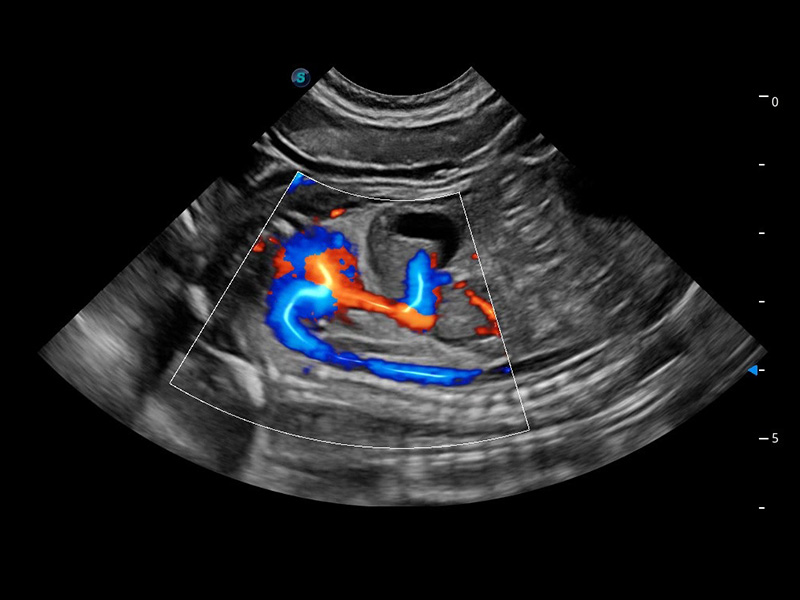

SR Flow 高分辨率血流成像

能够清晰显示细小、低速血流图像,获取传统彩色多普勒技术难以得到的细节和信息。

Micro F 显微血流成像

通过创新的Matrix E自适应滤波器和超长时间域算法,极大提升超低速微细血流的检出能力,同时更精准地滤除软组织和噪声信号,为兽用医生提供以往无法通过常规血流获得的疾病诊断信息。

优异的基础图像

(猫)髂动脉血流频谱